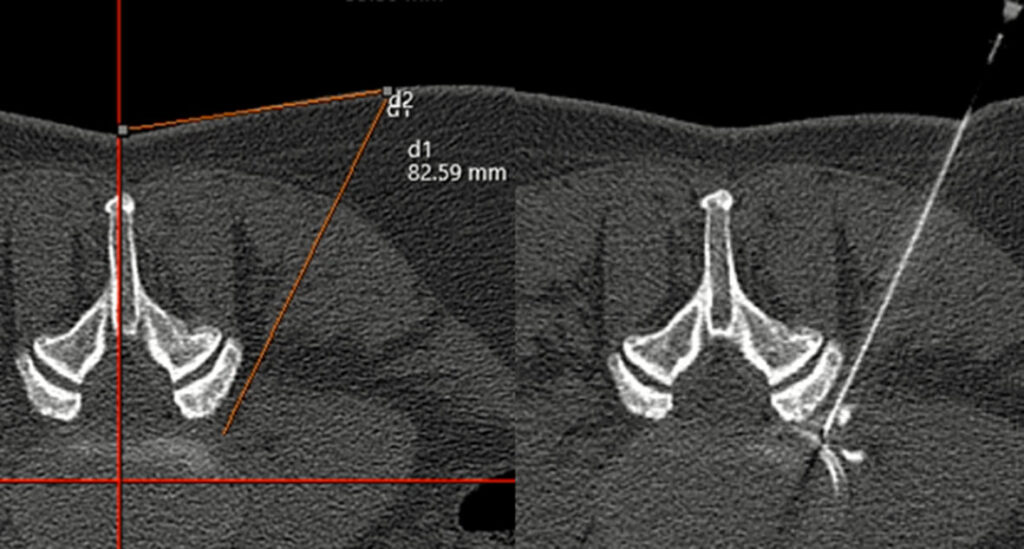

CT (Computertomographie)

→ CT Wirbelsäule und des Iliosakralgelenks nach Spondylodese

→ CT-gesteuerte minimalinvasive Schmerztherapie der LWS, ISG, Becken und Hüfte